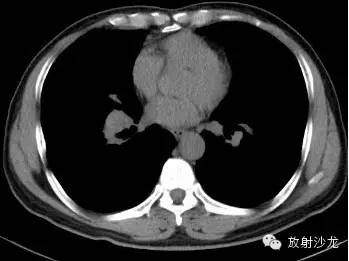

第一例:

44岁女性,因左乳腺结节行胸部CT检查发现胸部病变。

三幅图为典型的胸部结节病表现,肺门纵隔多发淋巴结肿大,各淋巴结不融合、不坏死、不侵犯邻近结构。右侧气管旁、右侧肺门、左侧肺门、主肺动脉窗淋巴结肿大,为1,2,3,4淋巴结。

双肺底见间质性病变。

CT拟诊结节病,呼吸内科建议定期观察。未经任何治疗11个月后复查示肺门纵隔淋巴结正常,双肺底间质性病变消失。左乳腺结节无变化(图略)